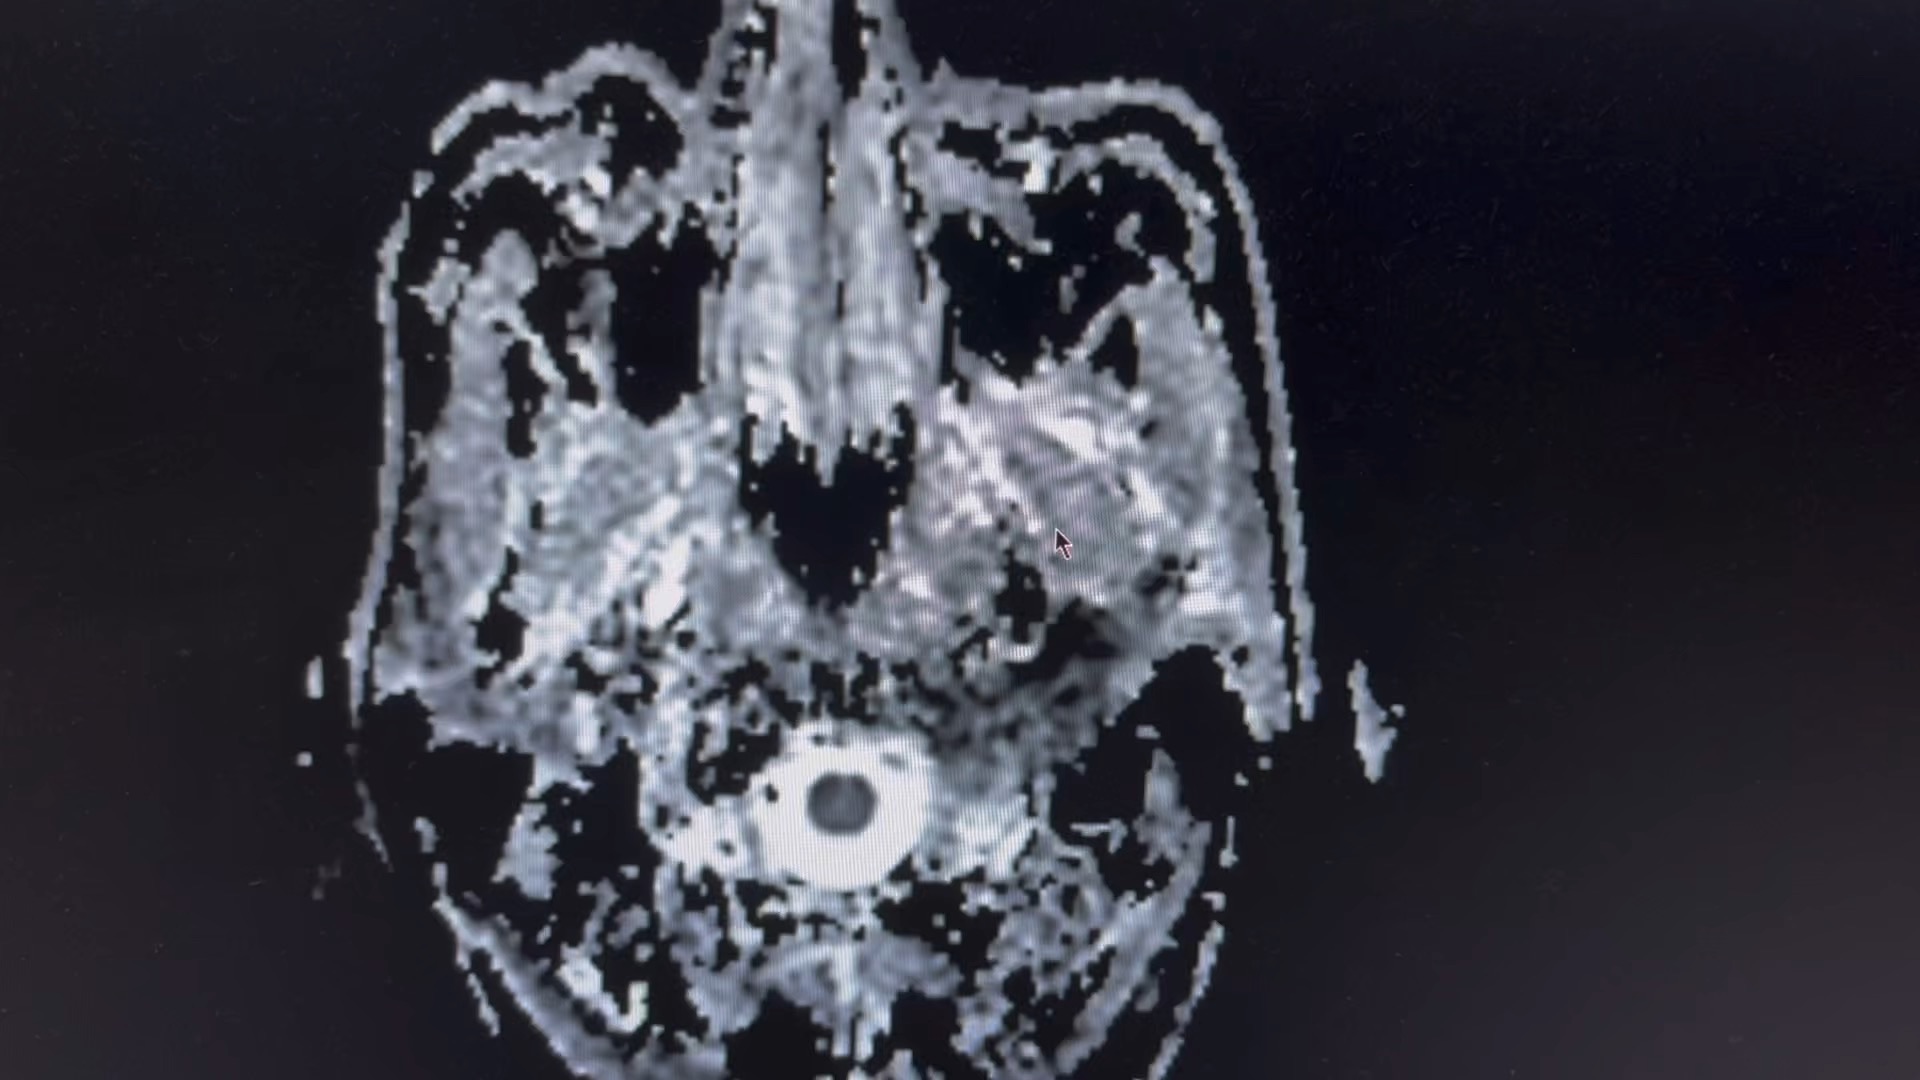

男,66 岁

突发剧烈头疼,呕吐伴意识模糊数小时。

一人在家,家属下班后发现患者情况不对,拨打 120 急诊入院,已转入脑介入科。